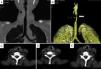

Caso 3Hombre de 44 años, con diagnóstico de GPA a los 39 años. Fue remitido a los 2 meses del diagnóstico de la GPA por presentar estridor laríngeo, disnea, sensación de cuerpo extraño en laringe y disfonía; la fibrolaringoscopia evidenció ESG del 20%, en el contexto de actividad sistémica (BVAS de 23 puntos). Recibió tratamiento con metilprednisolona 1g/día por 3 dosis y ciclofosfamida por vía intravenosa; se logró remisión de las manifestaciones sistémicas, con progresión de la disfonía, el estridor y la disnea. En su evaluación al mes, se visualizó en la TC un engrosamiento concéntrico circunferencial que obstruía parcialmente la luz traqueal (fig. 2 A y B). En la broncoscopia se documentó ESG del 70%, con estructuras laríngeas eritematosas. Recibió metilprednisolona 1g/día por 3 dosis más dilatación traqueal, con evolución clínicamente satisfactoria, remisión del estridor con mejoría sintomática. Sin embargo, a los 7 días presentó recidiva de los síntomas, reestenosis del 100% (fig. 2 C y D), que requirió traqueostomía de urgencia.

Tomografía computarizada laringotraqueal del caso 3. A y B) En los cortes axiales se aprecia la existencia de una estenosis subglótica con engrosamiento concéntrico circunferencial de la mucosa (*) que obstruye parcialmente la luz traqueal. C) Se observa una estenosis subglótica (flecha). D) Reconstrucción volumétrica estenosis subglótica (flecha).